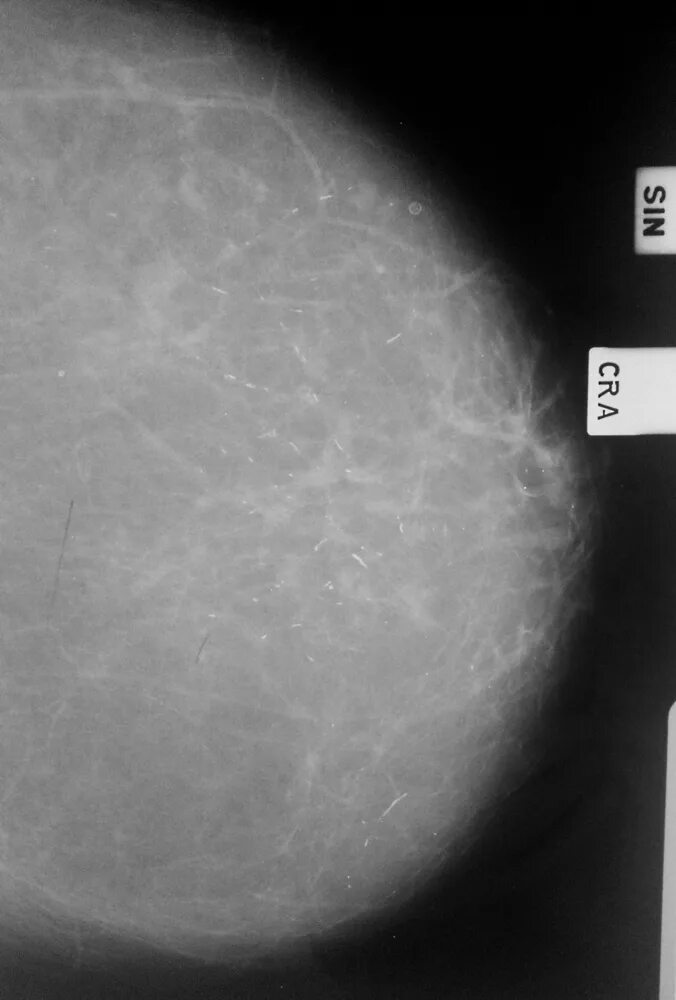

Причина образования кальцинатов